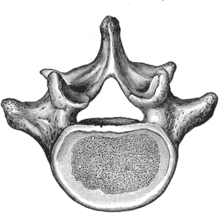

![]() A typical lumbar vertebra | |

The figure on the left depicts the general characteristics of the first through fourth lumbar vertebrae. The fifth vertebra contains certain peculiarities, which are detailed below.

As with other vertebrae, each lumbar vertebra consists of a vertebral body and a vertebral arch. The vertebral arch, consisting of a pair of pedicles and a pair of laminae, encloses the vertebral foramen (opening) and supports seven processes.

Body

The vertebral body of each lumbar vertebra is large, wider from side to side than from front to back, and a little thicker in front than in back. It is flattened or slightly concave above and below, concave behind, and deeply constricted in front and at the sides.[1]

Arch

The pedicles are very strong, directed backward from the upper part of the vertebral body; consequently, the inferior vertebral notches are of considerable depth.[1] The pedicles change in morphology from the upper lumbar to the lower lumbar. They increase in sagittal width from 9 mm to up to 18 mm at L5. They increase in angulation in the axial plane from 10 degrees to 20 degrees by L5. The pedicle is sometimes used as a portal of entrance into the vertebral body for fixation with pedicle screws or for placement of bone cement as with kyphoplasty or vertebroplasty.

The laminae are broad, short, and strong.[1] They form the posterior portion of the vertebral arch. In the upper lumbar region the lamina are taller than wide but in the lower lumbar vertebra the lamina are wider than tall. The lamina connects the spinous process to the pedicles.

The vertebral foramen within the arch is triangular, larger than the thoracic vertebrae, but smaller than in the cervical vertebrae.[1]

Processes

The spinous process is thick, broad, and somewhat quadrilateral; it projects backward and ends in a rough, uneven border, thickest below where it is occasionally notched.[1]

The superior and inferior articular processes are well-defined, projecting respectively upward and downward from the junctions of pedicles and laminae. The facets on the superior processes are concave, and look backward and medialward; those on the inferior are convex, and are directed forward and lateralward. The former are wider apart than the latter, since in the articulated column the inferior articular processes are embraced by the superior processes of the subjacent vertebra.[1]

The transverse processes are long and slender. They are horizontal in the upper three lumbar vertebrae and incline a little upward in the lower two. In the upper three vertebrae they arise from the junctions of the pedicles and laminae, but in the lower two they are set farther forward and spring from the pedicles and posterior parts of the vertebral bodies. They are situated in front of the articular processes instead of behind them as in the thoracic vertebrae, and are homologous with the ribs.[1]

Three portions or tubercles can be noticed in a transverse process of a lower lumbar vertebrae: the lateral or costiform process, the mammillary process, and the accessory process.[2] The costiform is lateral, the mammillary is superior (cranial), and the accessory is inferior (caudal). The mammillary is connected in the lumbar region with the back part of the superior articular process. The accessory process is situated at the back part of the base of the transverse process. The tallest and thickest costiform process is usually that of L5.[2]